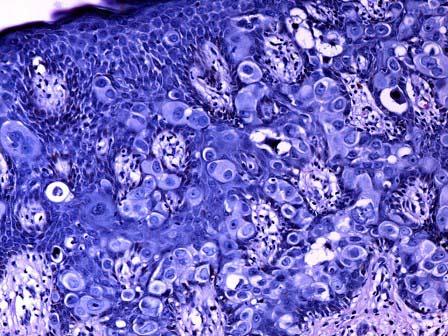

问题 女性,30岁,乳头呈湿疹样。手术切除,镜下表皮内可见非典型细胞增生,细胞呈小簇状分布,中央密集(如图)。最有可能的诊断为 ( )

选项 A.乳头派杰病 B.恶性黑色素瘤 C.鳞癌 D.乳头腺瘤 E.汗管瘤样腺瘤

答案 A